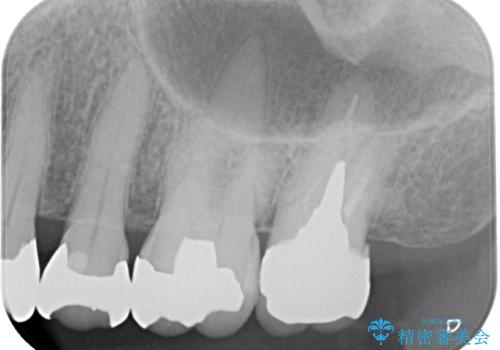

- 被せものに穴が開いたとのことで来院された患者様です。被せものをやり替えることになったので、かみ合わせが強い方のでPGAクラウンをご提案しましたが患者様の強いご希望によりオールセラミッククラウンによる補綴治療を行っていくことになりました。

拡大鏡視野下で、金属の被せもの、虫歯の除去を行い、オールセラミッククラウンに適した形に整えました。

歯と歯茎の間に圧排糸と言われる糸を入れてシリコーン印象材にて型どりをしました。

患者様のご希望により、根管治療、土台のやり替えは行っていません。